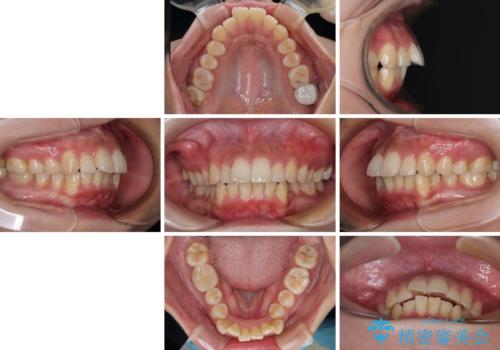

- 前歯のデコボコと口元の突出感を気にして来院された患者様です。

上下前歯がくちばしのように突出していたため、上下左右の第一小臼歯4本を抜歯し、ワイヤー装置にて矯正治療を行うこととしました。